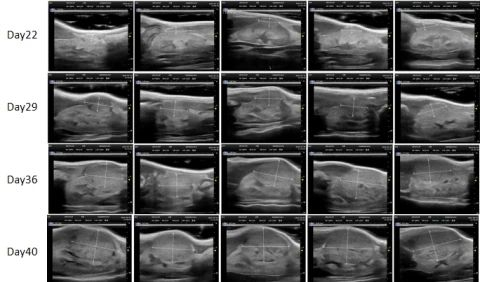

PDX Model (Growth Curve)

部分不朽情缘mg官网PDX原位模型展示